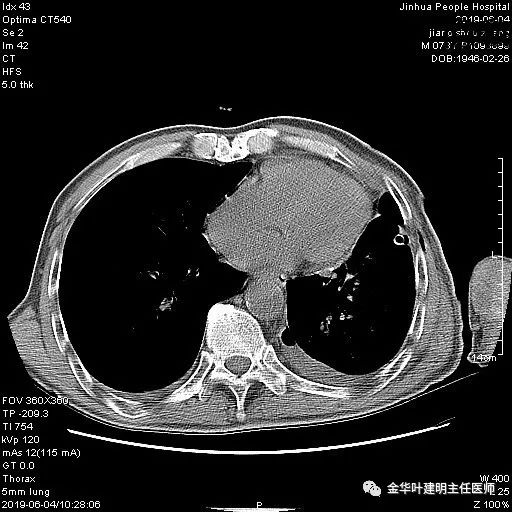

6.4上午:24小时引流出血性乳糜液1800毫升。是否再次手术进行右进胸胸导管结扎,抑或继续保守治疗非常纠结!压力非常大!!多方讨论会诊无法取得一致意见,但一般认为,引流量在1000毫升以上宜积极手术。情况与浙二医院范军强教授联系,请求指导,范教授认为左侧肺手术,损伤胸导管主干的机会较小,多数可保守治疗而愈。在他们的病例中,也有结扎胸导管后引流量仍无减少,效果并不能完全保证。建议可以考虑胸管夹管观察(因为淋巴管压力低,予以适当的压力,漏出量可能会明显减少),同时继续禁食,并静脉营养支持,引流管口可能会有渗液,注意更换敷料。与家属充分沟通后决定试夹管;这天血色素9.0 g/L;胸部CT复查示: